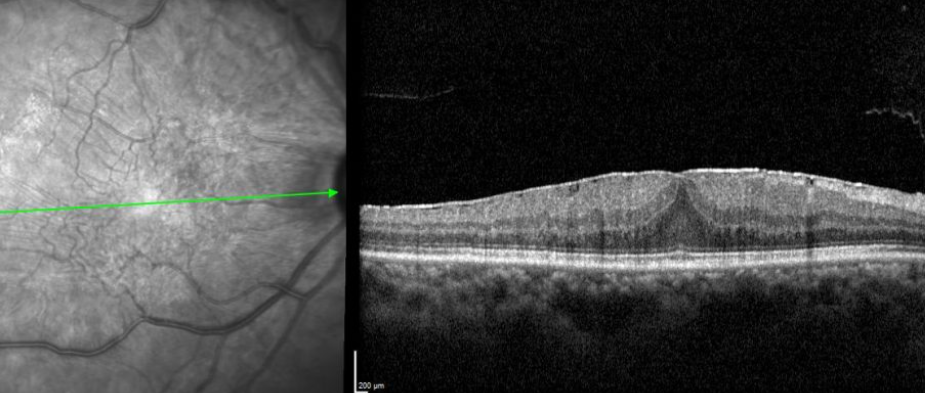

• Optical coherence tomography (OCT): A non-invasive imaging test that provides detailed cross-sectional images of the retina, helping to assess the thickness and extent of the membrane.